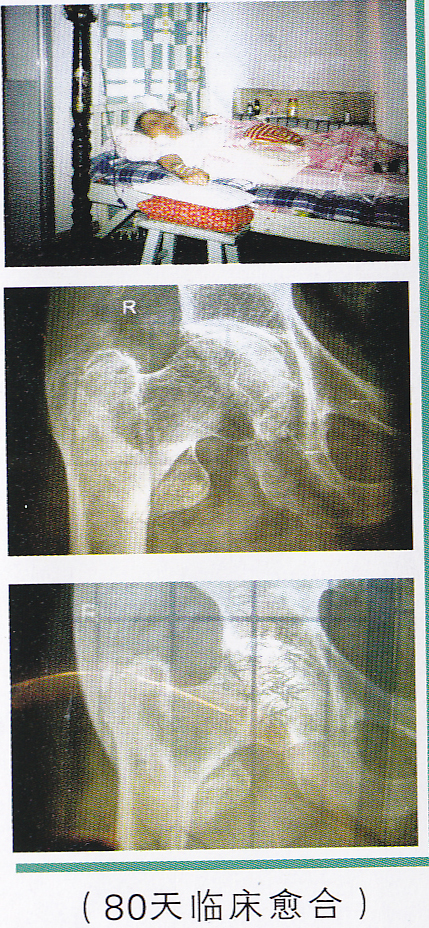

非手术治疗老年人股骨颈骨折 肌骨颈骨折是一种常见于老年人的损伤,但也见于青壮年和儿童。老年人发病女性较多,此骨折愈合较慢,虽经各种相应措施治疗,仍有部分患者无法愈合。因局部解剖关系,股骨头血液供应较差,无论骨折处能否愈合,均易发生缺血性坏死,坏死率在30%左右。 中医中药有不可替代的优势。通过多年临床验证,笔者在祖传基础上研究出一套治疗老年人股骨颈骨拍的中药方剂、方法,克服了骨质疏松、持续牵引导致骨不愈合的难题,治愈率高,无需手术,既经济又减轻了患者的痛苦。